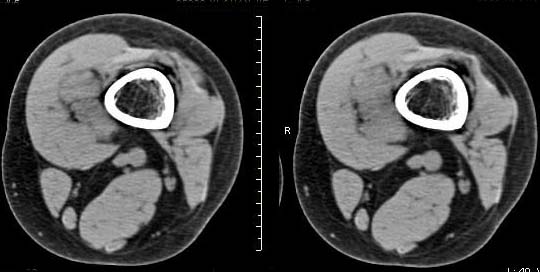

女,24岁,左大腿下部近膝关节处偏内侧有一软组织包块,触之有压痛,平扫示病灶密度不均,形态及轮廓欠规则,无包膜,与周围组织界限不清,增强后显示有明显强化且不均匀强化,本人考虑为该软组织肿块为恶性病变。请大家发表高见!

病灶是有不均匀强化,但病灶与周围组织分界较清,恶性可能。

病理结果:血管瘤。

血管瘤,增强延迟扫描。